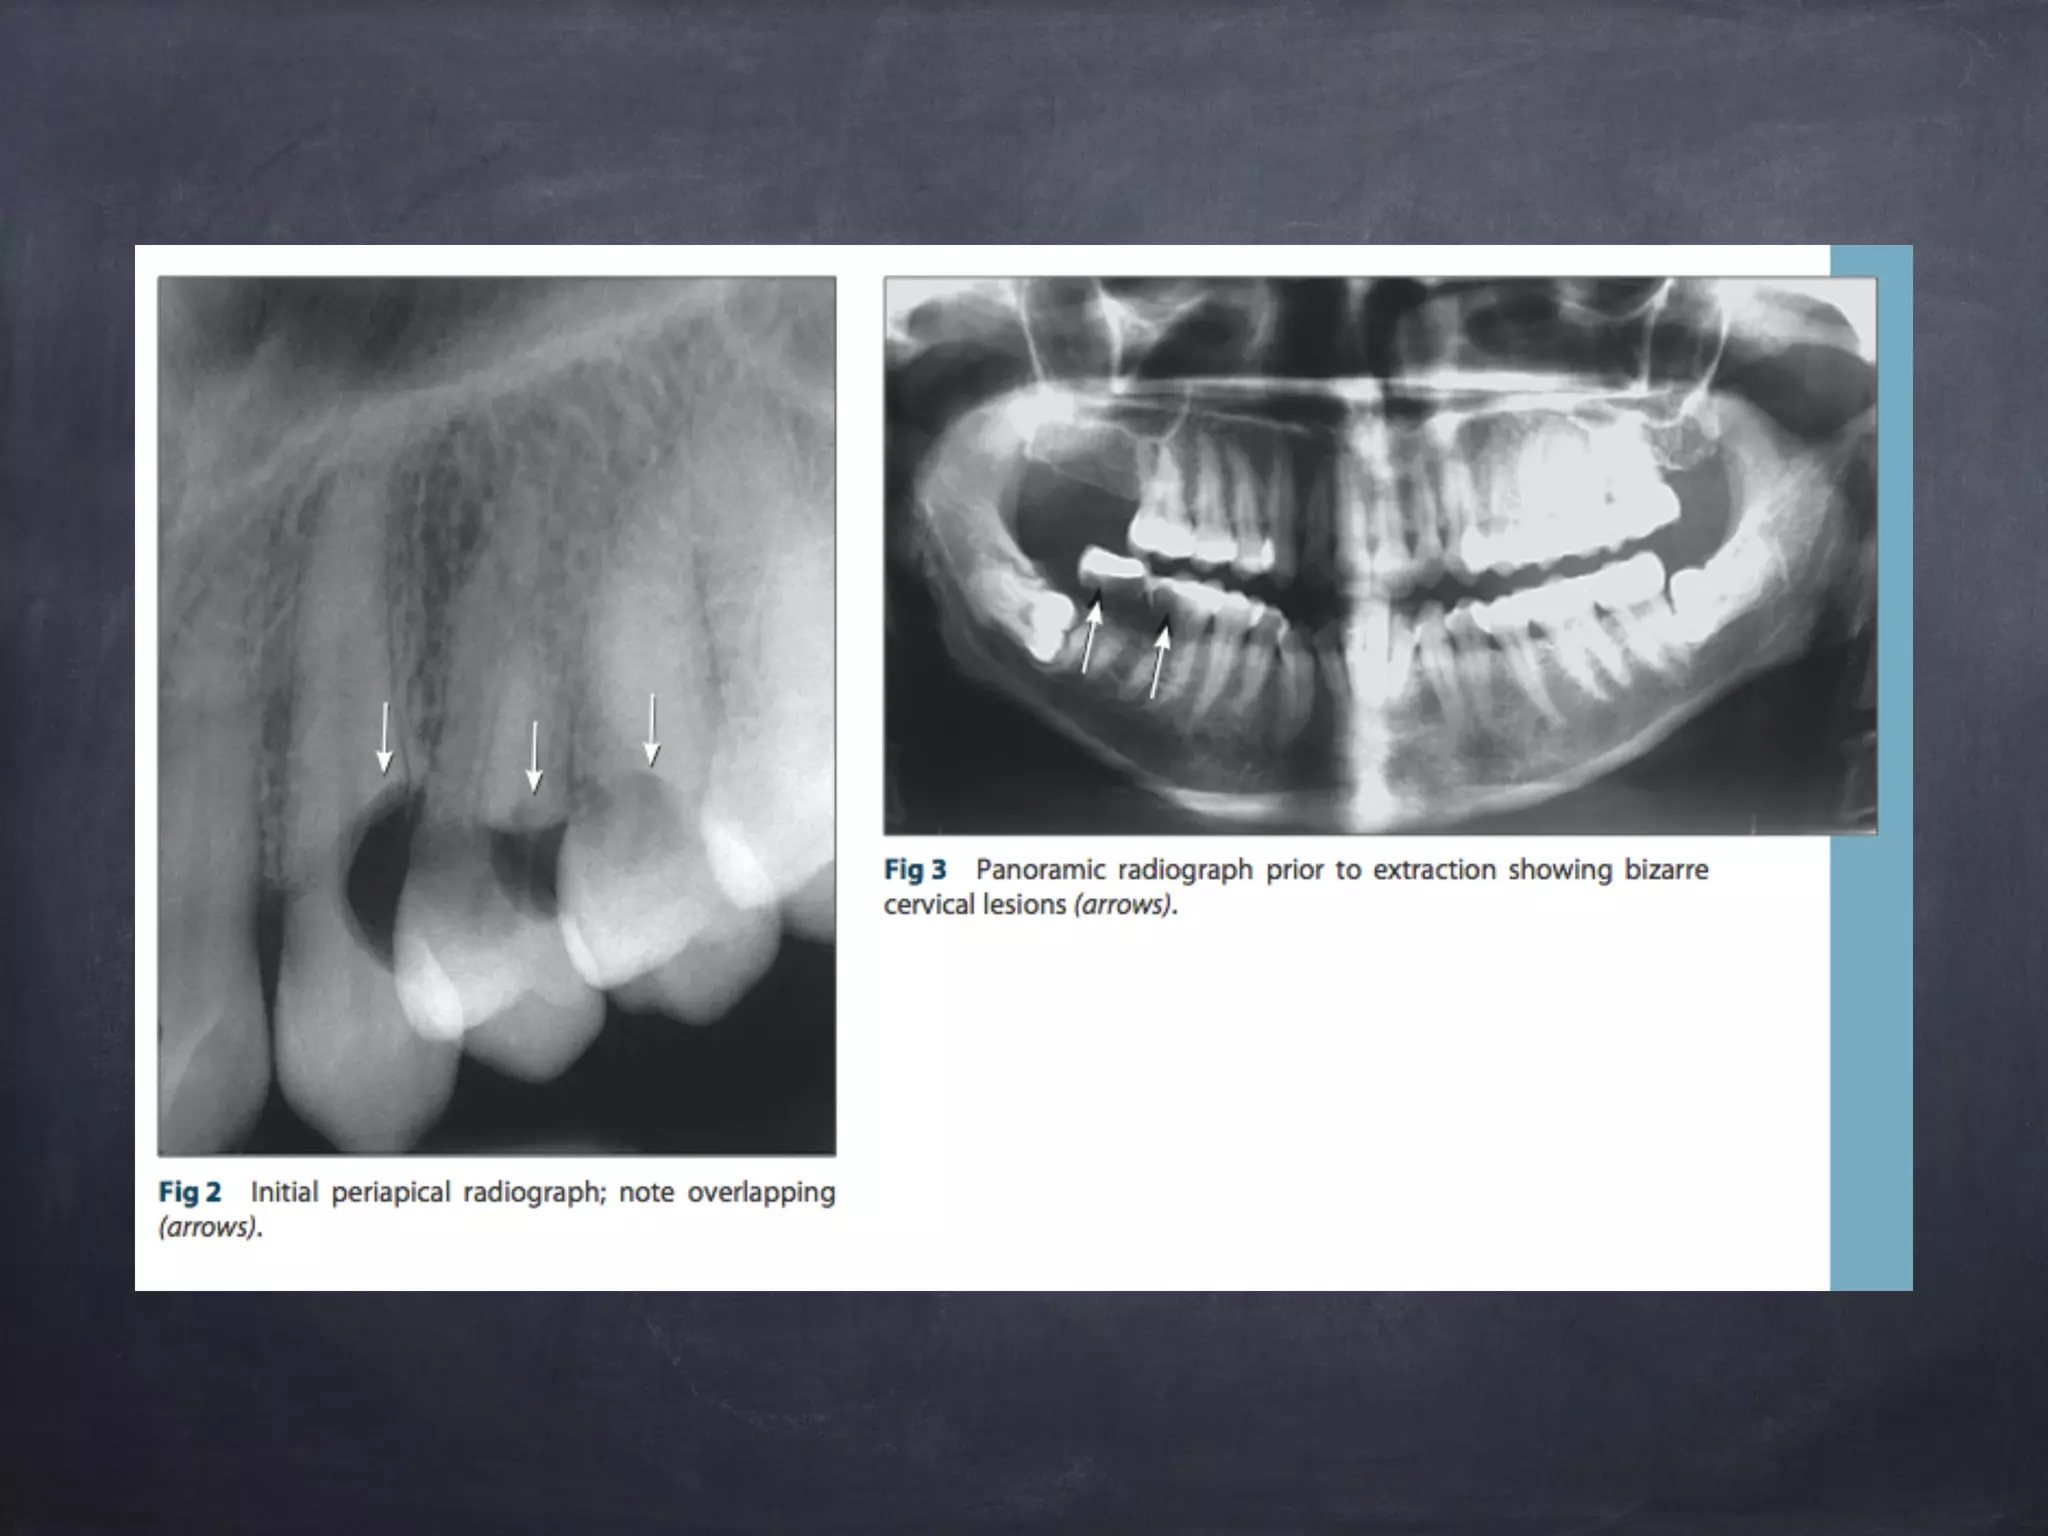

พบรอยโรคโปร่งรังสีที่บริเวณคอฟัน ฟันซี่

12MD,13M,22MD,23M,31MD,32MD,33MD,

41MD,42MD,43MD,34MD,35MD,36MD,

48M

Panoramic

Differential

diagnosis

dental caries

root resorption

after radiation multiple invasive

cervical resorption

Eisbruch, A., Ten Haken, R.K., Kim, H.M., Marsh, L.H., Ship, J.A. (1999) Dose, volume, and

function relationships in parotid salivary glands following conformal and intensity-modulated

irradiation of head and neck cancer. Int J Radiation Oncol Biol Phys, 45, 577-587

Radiologist

consultation

ลักษณะรอยโรคไม่เหมือนกับโรคฟันผุ แต่มีลักษณะ

คล้ายกับการ resorption เนื่องมาจากการเห็น

ขอบเขตที่ชัด และตำแหน่งของการเกิดโรค

impression for multiple cervical

resorption